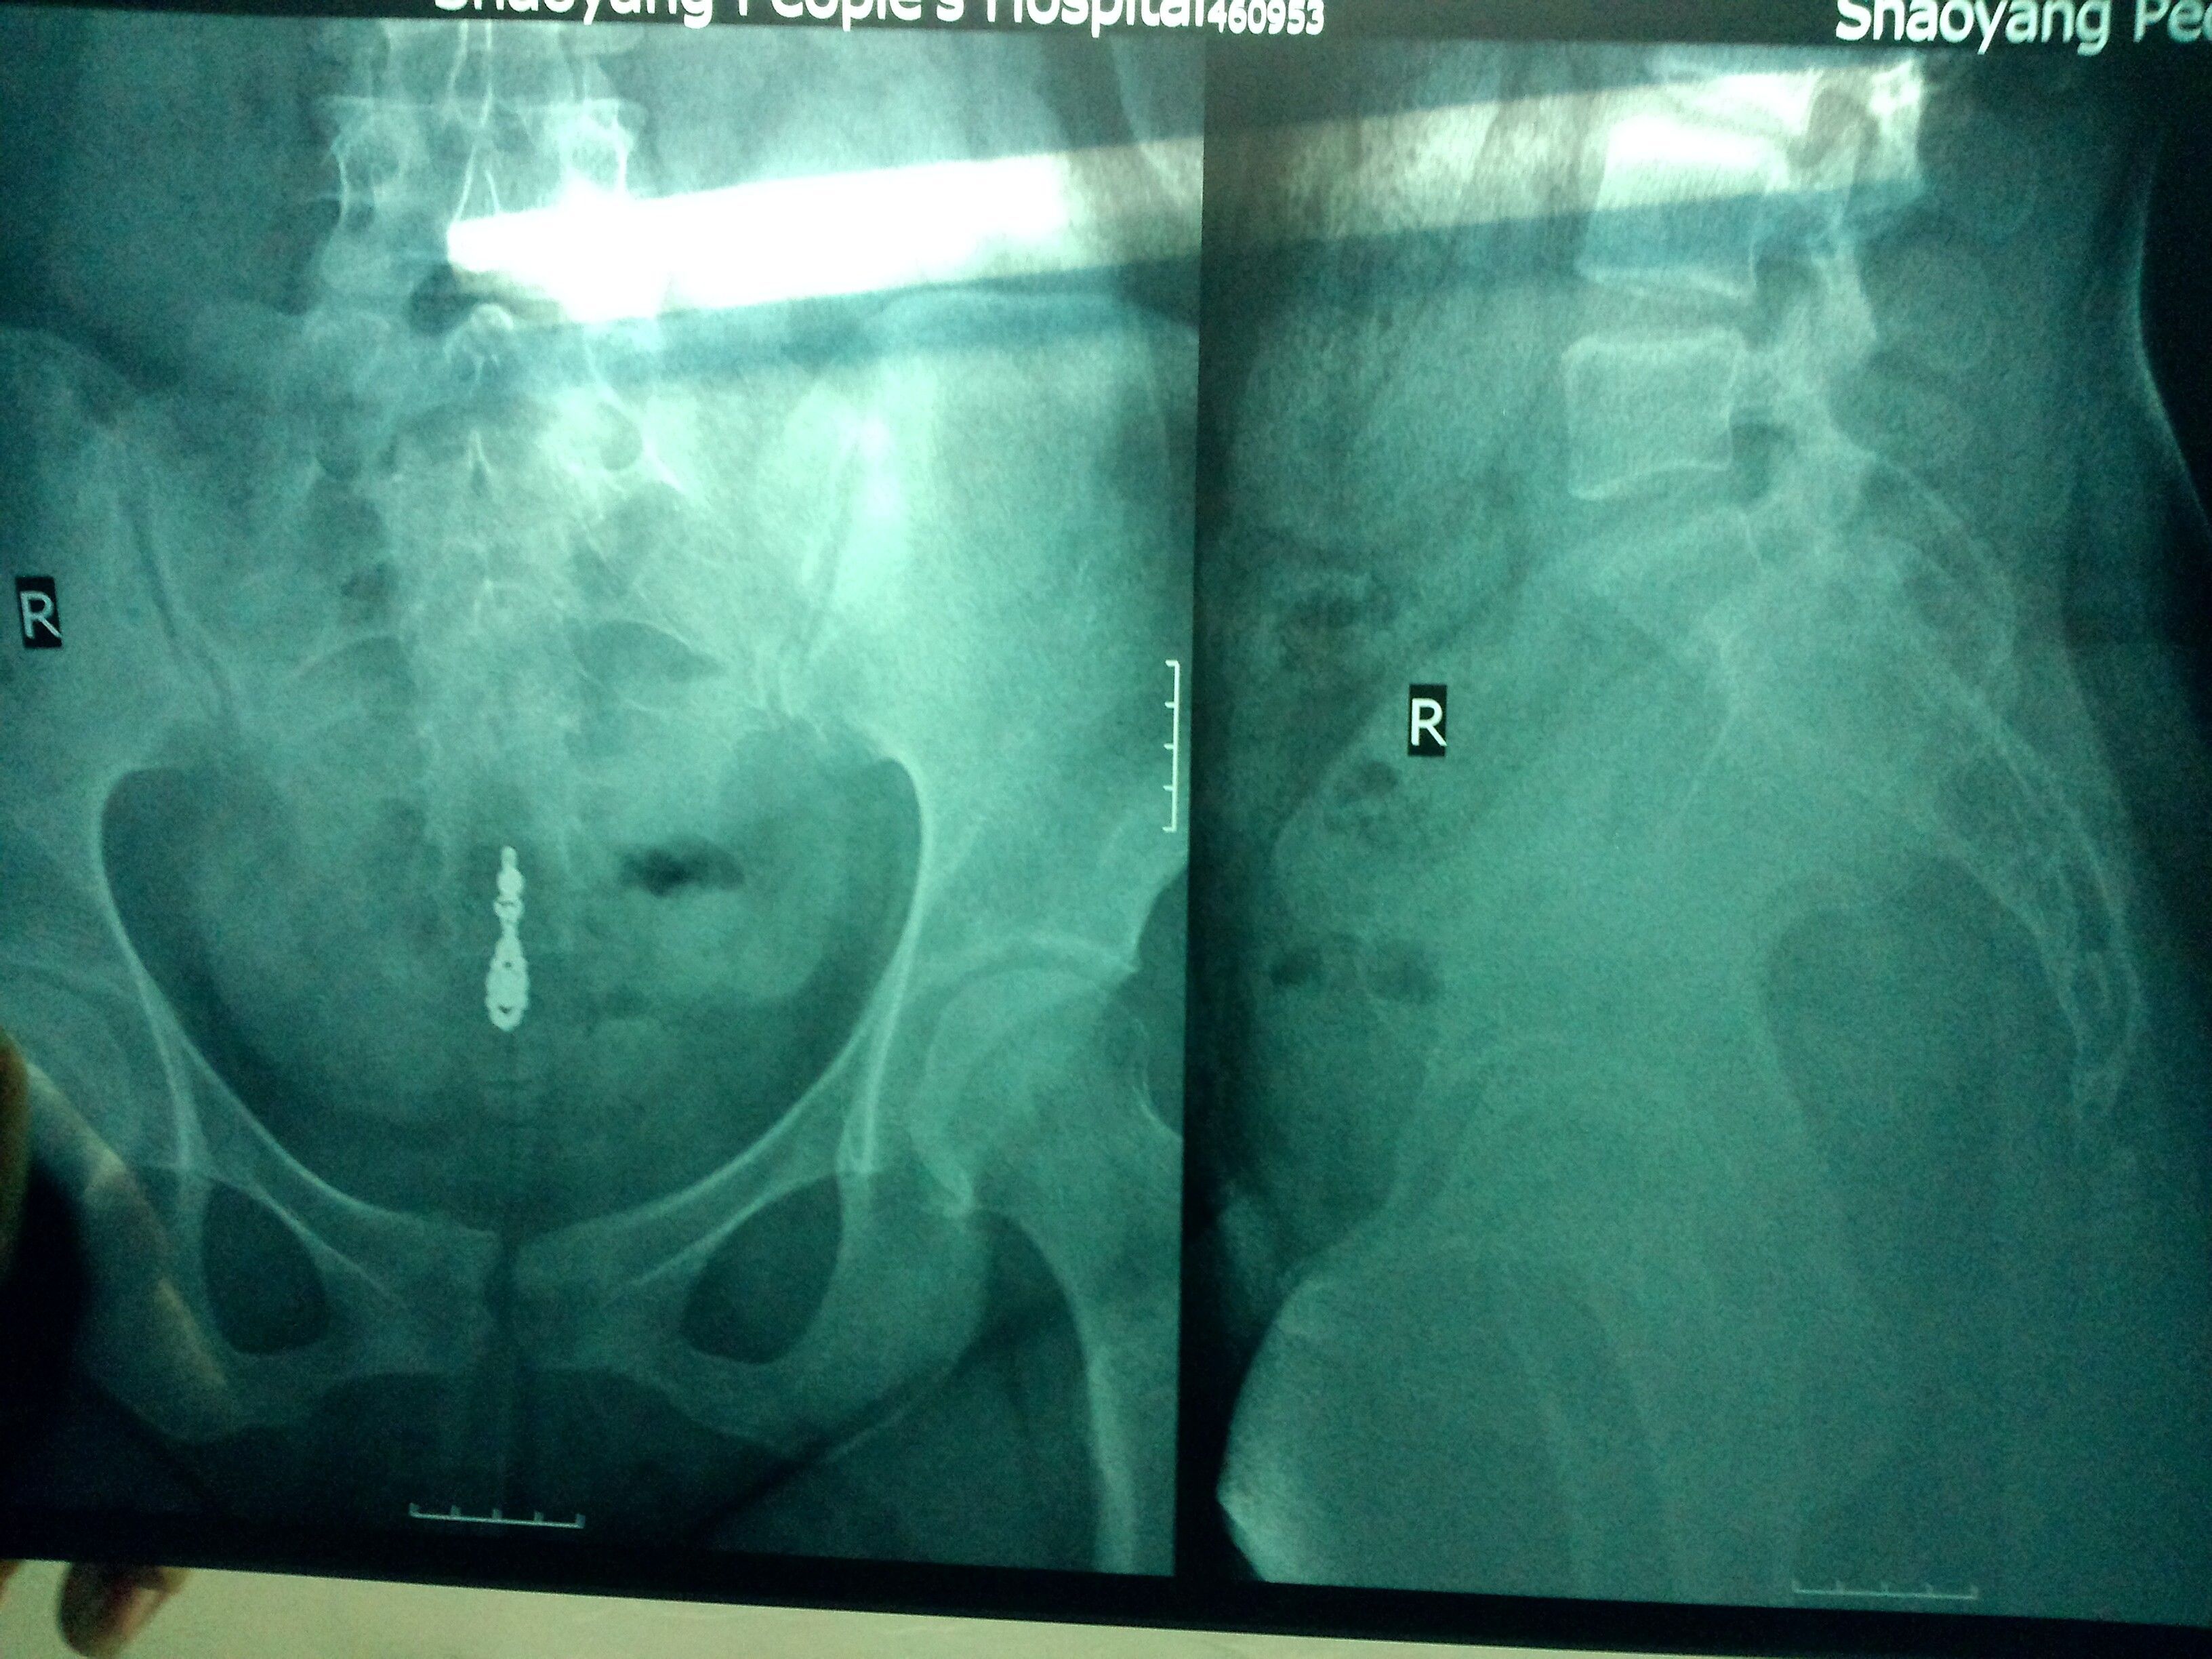

骶尾骨移位后生小孩能顺产吗?如要不能还能正过来吗?我去年到昨天为止一共摔了3次,第一次摔到痛了很久,坐久了就痛,昨天又摔到了,很痛,今天到医院照了X片,请医生帮忙看看,听别人说摔倒这里很严重的,生小孩不能顺产,但是我想顺产有可能吗?平时还需要注意些什么,如睡觉躺着还是侧睡?